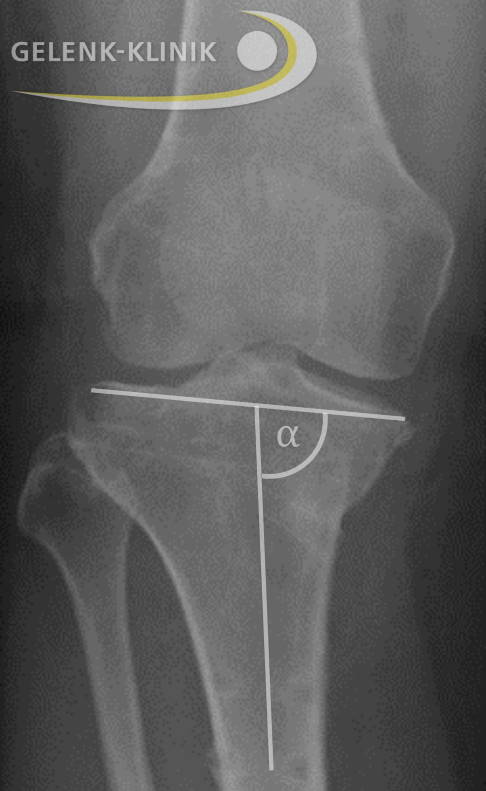

Die Technik zur Korrektur bzw. Umstellung der Beinachse ist abhängig vom genauen Ort der Fehlstellung. Am häufigsten ist der kniegelenknahe Anteil des Schienbeins (proximale Tibia) betroffen. Nur etwa 10 % der Fehlstellungen entfallen auf den unteren Anteil des Oberschenkelknochens (distaler Femur). Dies erfasst der Operateur vor einem Eingriff durch exakte Bestimmung der Beinachse und der Gelenkwinkel.

Bei einer O-Bein-Stellung fällt die Gelenklinie im Verhältnis zum Schaft des Unterschenkels häufig zu stark ab. In diesem Fall öffnet man das OP-Gebiet auf der Knieinnenseite am Schienbeinkopf.